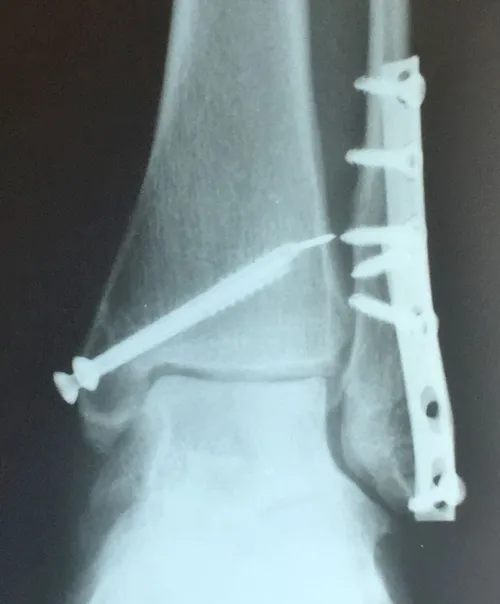

Preop and Postop ORIF Posterior Malleolus Fracture with associated Fibular fracture

Preop

Postop